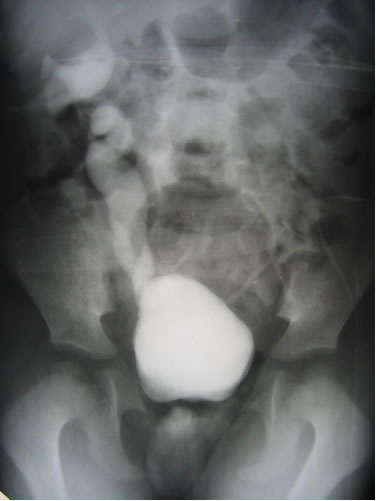

Цистография